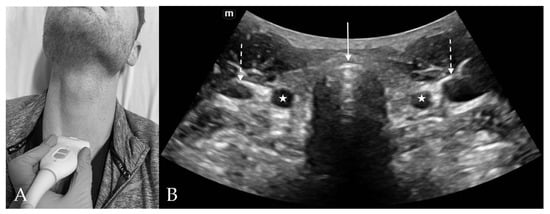

3. Probe Selection and Technique

4.3. Thyroid View

6. Confirmation of Endotracheal Intubation